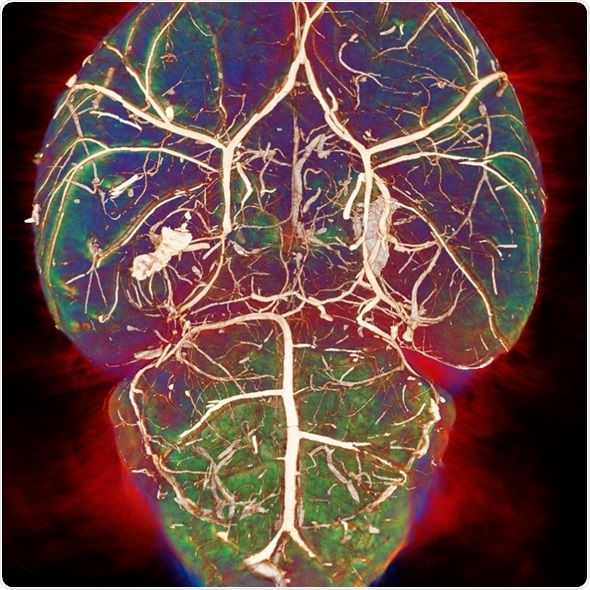

Each modality looks at tissue in a different way. For example, MRI has very good soft tissue contrast and there is a number of parameters that are associated with different pathologies.

For example, there are T1 and T2 changes in cancer and neurodegenerative diseases, whereas, with a modality like CT, there's less soft tissue contrast and it would be used more to look at things like bone structure. It uses a different type of contrast and produces images through a different physical mechanism.

By using different modalities, we can get much more information compared with using only one modality.

The MRI has a very good soft tissue contrast. The parameters that I generally look at using MRI are called T1 and T2. These vary in different tissues, obviously, but also across different pathologies. MRI provides very high sensitivity to these pathologies, which can't be seen using other modalities.

Image credit: Photoacoustic imaging group, UCL